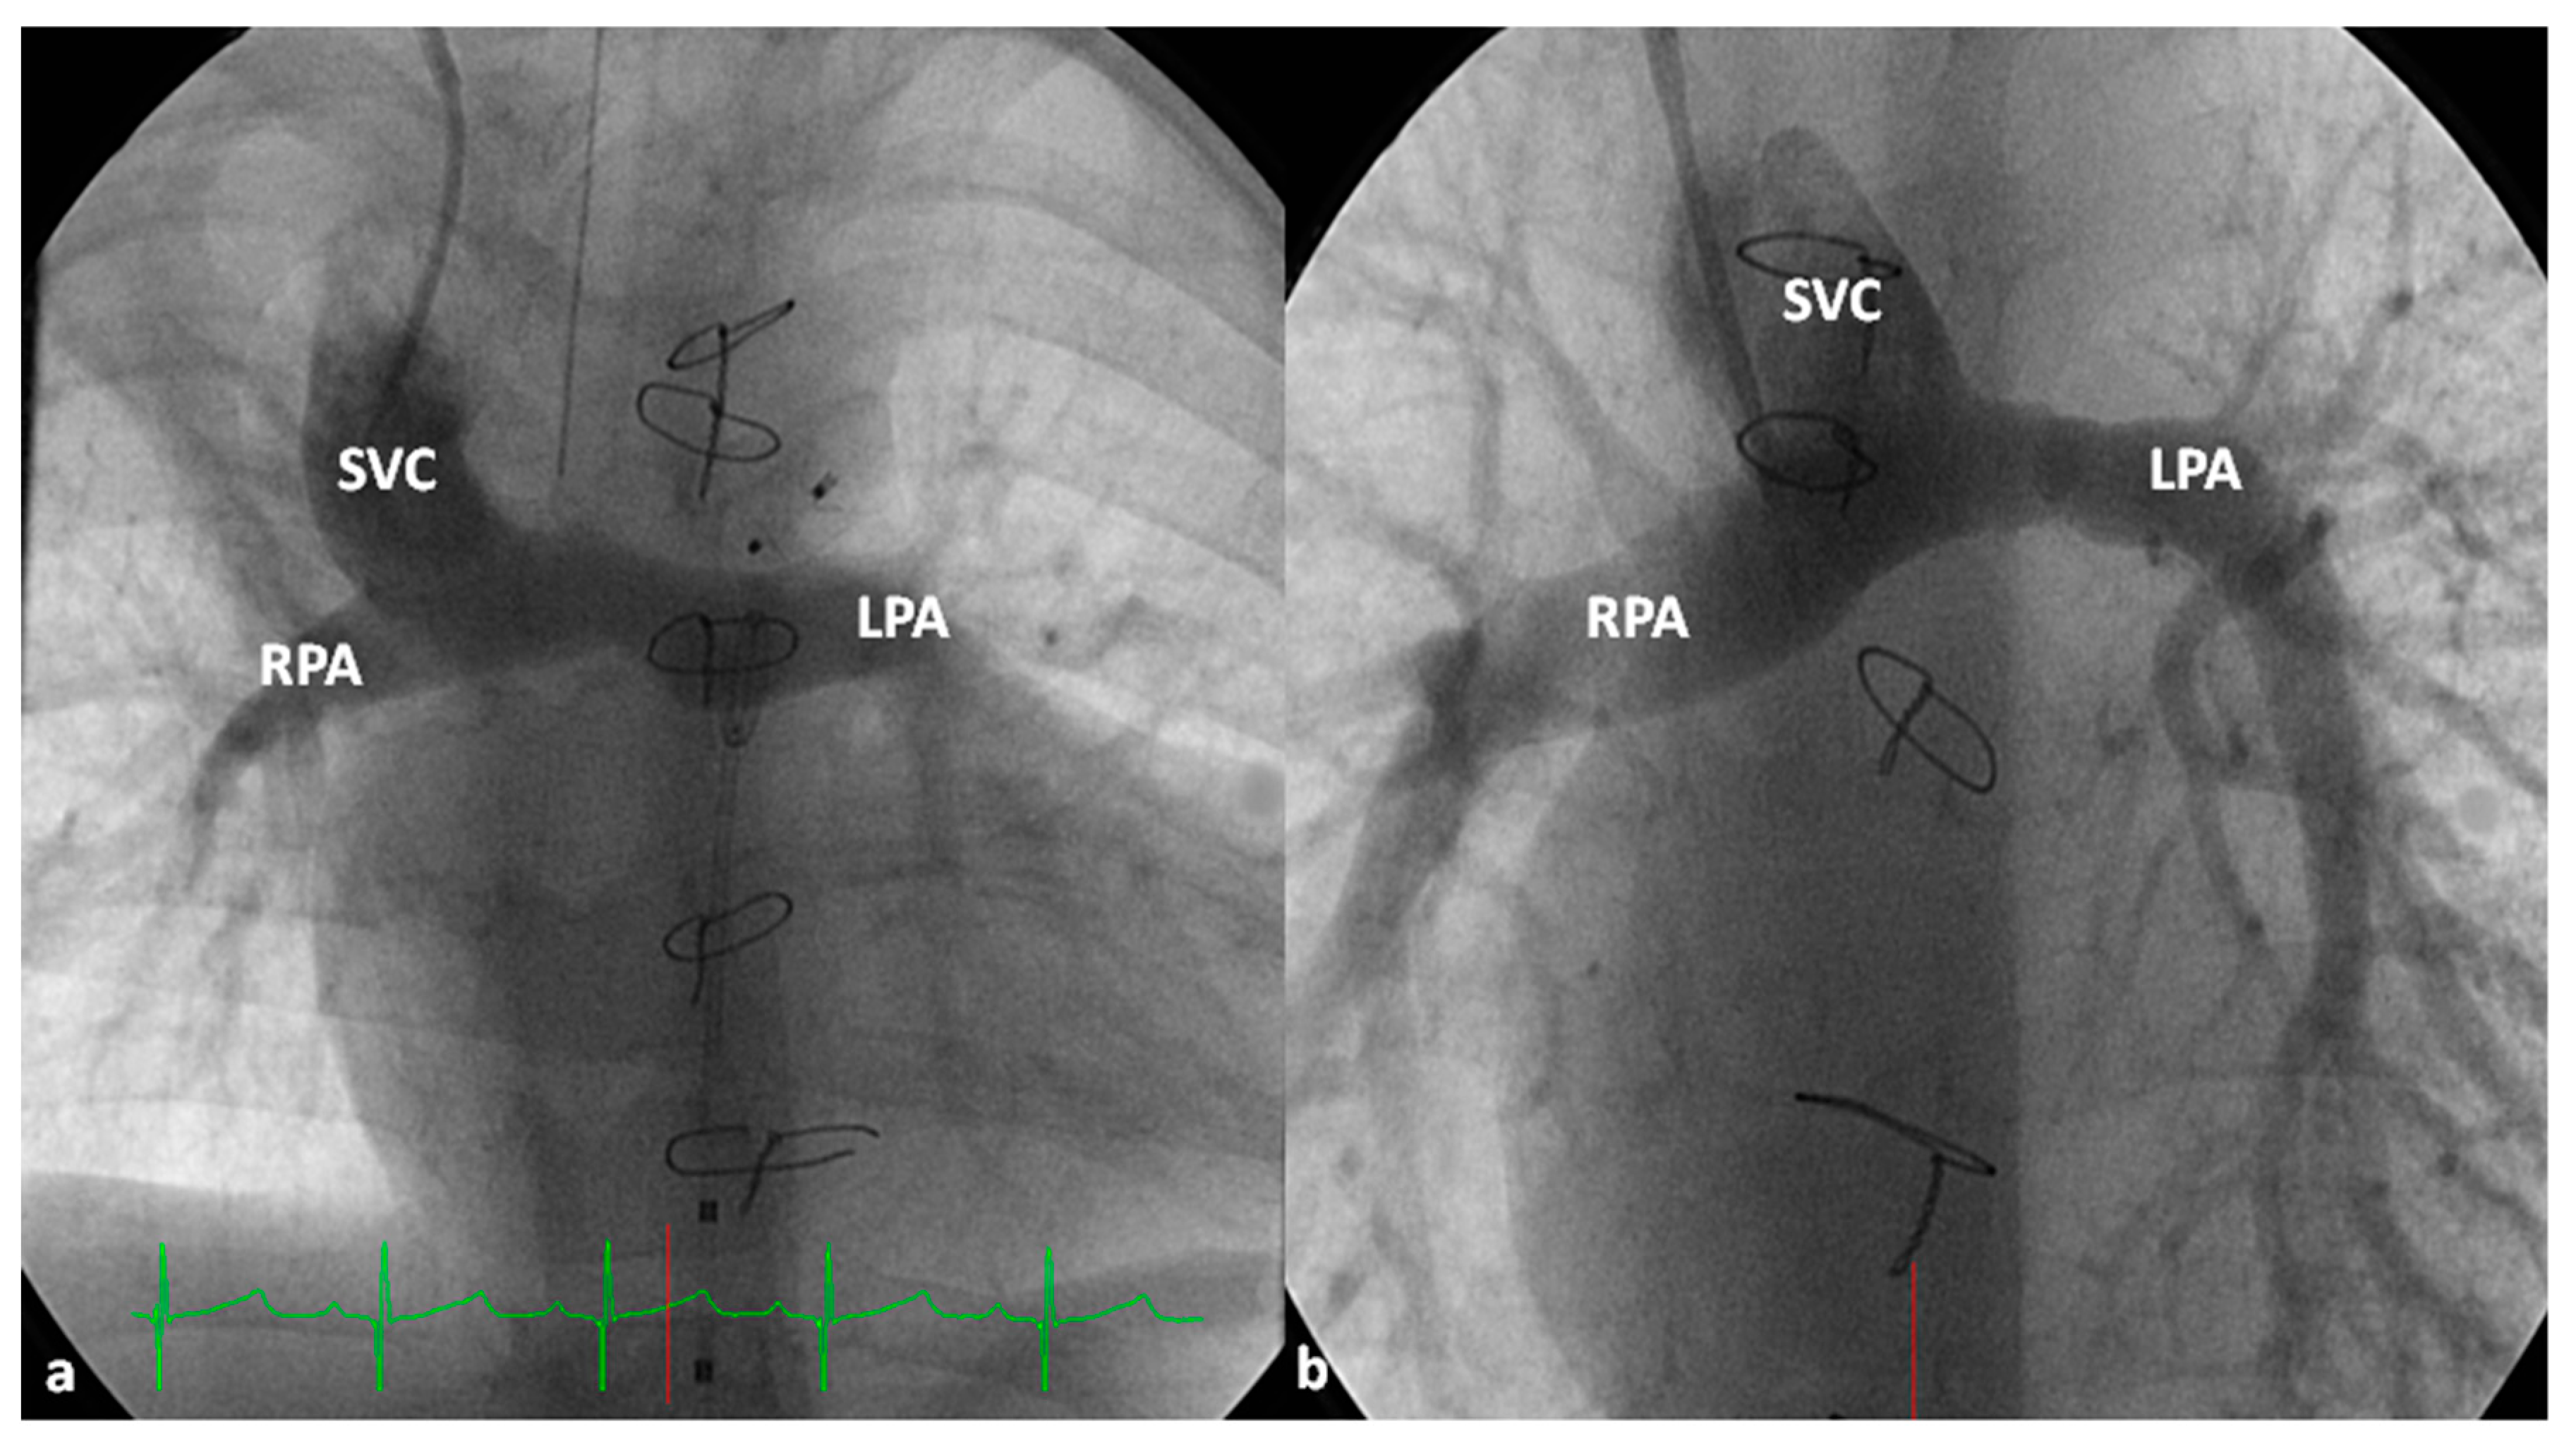

4.2.2. Stage II

At about the age of six months, a bidirectional Glenn procedure [80] is performed. In this procedure, the superior vena cava (SVC) is disconnected from the right atrium and anastomosed to the PA so that the blood from SVC is directed into both branch PAs, thus the name bidirectional Glenn (Figure 8).

In patients with an additional persistent left SVC, a bilateral, bidirectional Glenn procedure (Figure 9) is performed especially if the bridging left innominate vein is small or absent.

Prior to the bidirectional Glenn procedure, normal pulmonary artery pressures should be documented either by echo-Doppler or cardiac catheterization studies. In cases with PA stenosis and mitral valve regurgitation, these abnormalities should also be repaired at the time of bidirectional Glenn procedure. Subaortic stenosis, if present, should also be bypassed by Damus–Kaye–Stansel. If there are any other hemodynamically significant abnormalities, they should also be addressed at this stage.